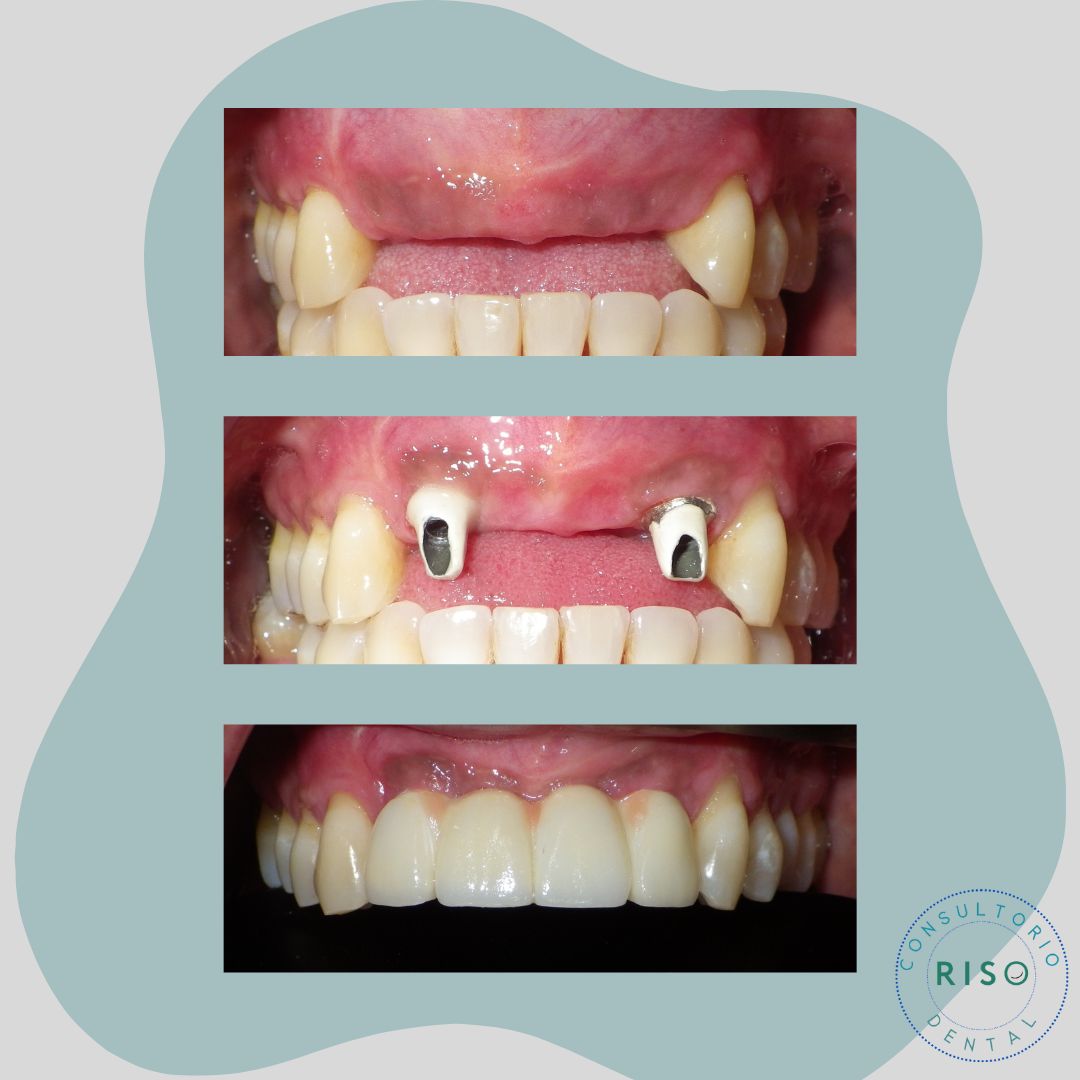

• Prostodoncia

• Rehabilitación bucal

• Implantología dental